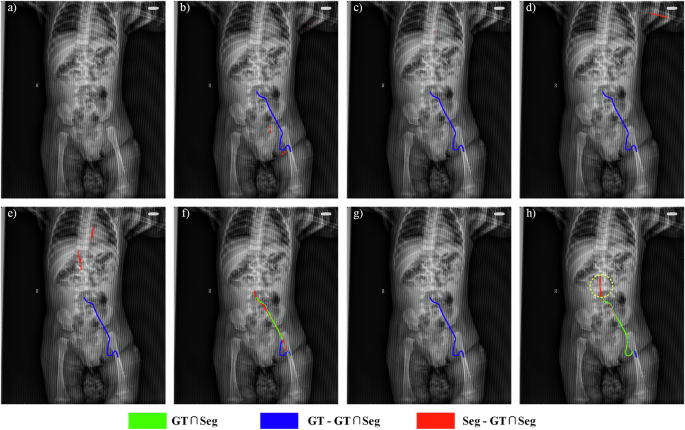

Upper extremity PICC segmentation: Fig. 2 shows an original image and corresponding segmentation results for a representative pediatric upper extremity PICC radiograph from Center I, as yielded by DFANet, FSNet, MDANet, MISSFormer, RSF-Conv, UNet++, and TopNet. Within these segmentation overlays, green indicates correctly identified PICC regions (true positives), red corresponds to false detections, and blue highlights missed target areas (false negatives). Compared to standard adult chest X-rays, the pediatric radiograph in Fig. 2a is slightly tilted and exhibits substantial occlusions, particularly along the right and inferior regions, which significantly complicate PICC detection. The thin structure of the PICC and its frequent overlap with bony structures make complete segmentation challenging. For example, discontinuous segmentation manifests as gaps within green areas, as seen in (b). Incomplete segmentation is evident in (c), (d), and (g), with model (g) failing entirely to identify the PICC. False positives (red regions) are present in (c), (f), and (h). Notably, these erroneous detections in (c) and (f) occur near the PICC tip, while those in (h) are mainly localized to the right side of the catheter. These observations underscore the superiority of TopNet over baseline models.

a Original upper extremity PICC radiograph from an infant / toddler from Center I. b–h Segmentation results obtained using different methods: DFANet, FSNet, MDANet, MISSFormer, RSF-Conv, UNet++, and TopNet (proposed). Green suggests correctly identified areas (correct detections), red denotes false detections, and blue marks undetected target regions (missed detections).

Lower extremity PICC segmentation: Fig. 3 displays a representative pediatric lower extremity PICC radiograph from Center I, comparing the original image with segmentation results from several methods. The original image (a) contains severe streak artifacts that considerably impair the segmentation performance of baseline approaches. As shown by the blue regions in (b–e) and (g), DFANet, FSNet, MDANet, MISSFormer, and UNet++ completely fail to detect the PICC line. Although RSF-Conv achieves accurate delineation of the catheter, it results in discontinuous segmentation and misidentification (f). In contrast, TopNet eliminates these discontinuities and false positives, while also detecting clinically relevant catheter segments that were omitted in the manual annotations. In (h), blue represents expert-annotated regions, while the yellow dashed circle highlights the actual PICC region that was absent in the manual reference. This demonstrates the ability of our approach to identify genuine PICC line features that were initially overlooked during annotation.